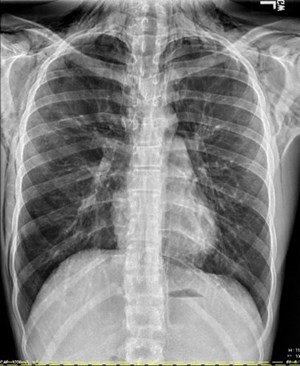

2nd Place Emage Winner: Fibrosing Mediastinitis